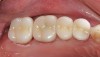

Tissue management was then obtained by the application of the same putty-type retraction system (Figure 8). After 2 minutes, the putty retraction material was thoroughly rinsed away with air/water spray and dried. The teeth were then cleaned again with 2% chlorhexidine, rinsed, and dried without reaching desiccation.20 The restorations were filled with a dual-cure resin cement system, Maxcem™ (Kerr Corporation, Orange, CA), seated, and remained undisturbed for 90 seconds before light-curing (Figure 9).6 This waiting period was mandatory for the self-adhesive chemistry in the cement to be fully effected. The cement reached a gel state and was easily removed with a handscaler (Figure 10). To ensure no movement of the restorations while cleaning cement interproximally, the restorations were tacked down mid-cervically on the buccal with a 4-mm turbo tip in a LED curing light. Interproximal cleaning was accomplished with waxed floss (Figure 11) and final curing was performed on both the buccal and lingual aspects with two LED lights simultaneously for 20 seconds (Figure 12), followed by occlusal curing for 20 seconds. Marginal finishing was performed with an 8-fluted carbide bur and composite points and cups. Interproximal finishing involved using medium- and fine-composite finishing strips. Occlusion was checked and slight adjustments were performed before the final polishing of these areas with porcelain polishing points. The final results are shown in Figure 13 and Figure 14.

44_Figure14